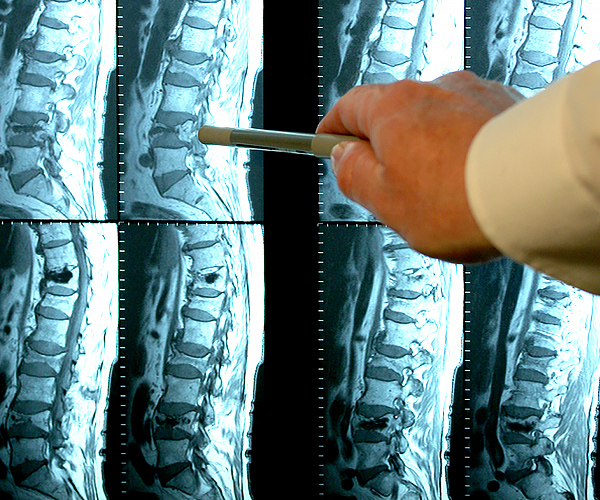

Restauration de l'articulation du coude. Patiente, 31 ans. Durée du traitement par la Marukaya Сream : 12 jours. Son articulation est entièrement restaurée :